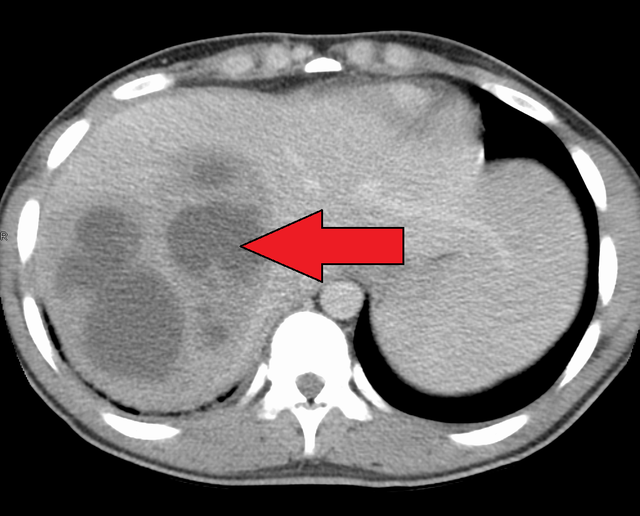

Pyogenic liver disease is an underdiagnosed disease. It is also a common cause of pyrexia of unknown origin. Pyogenic liver disease arises secondary to cholangitis, hematogenous spread, direct extension of gallbladder abscess, or through penetration or non-penetrating trauma. Pyogenic liver abscess can complicate appendicitis, colon disease, and dental sepsis. The common causative agents are E. coli, streptococcus milleri, and bacteriodes. The patient may present with fever, right upper quadrant pain and tenderness which may radiate to right shoulder. Chest x-ray may show raised right hemidiaphragm. Ultrasound guided aspiration and/or drainage are mainstay of management. Reference: Davidson's Principles and Practice of Medicine Image via: https://en.wikipedia.org/wiki/Pyogenic_liver_abscess